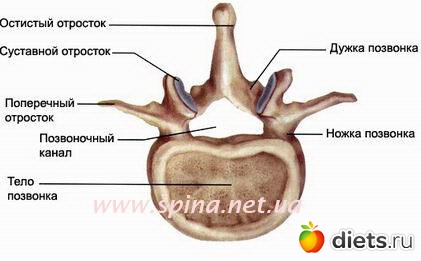

Позвонки - это кости, которые формируют позвоночный столб. Передняя часть позвонка имеет цилиндрическую форму и носит название тела позвонка. Тело позвонка несет основную опорную нагрузку, так как наш вес в основном распределяется на переднюю часть позвоночника. Сзади от тела позвонка в виде полукольца располагается дужка позвонка с несколькими отростками. Тело и дужка позвонка формируют позвонковое отверстие. В позвоночном столбе соответственно позвонковые отверстия расположены друг над другом, формируя позвоночный канал. В позвоночном канале расположен спинной мозг, кровеносные сосуды, нервные корешки, жировая клетчатка.

От дужки позвонка отходят семь отростков: непарный остистый отросток и парные поперечные, верхние и нижние суставные отростки.